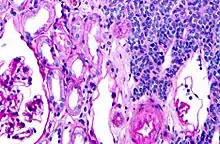

| Micrograph of a metanephric adenoma with structures reminiscent of those seen in papillary renal cell carcinoma. H&E stain. | |

Metanephric adenoma is diagnosed histologically. The tumours can be located at upper pole, lower pole and mid-hilar region of the kidney; they are well circumscribed but unencapsulated, tan pink, with possible cystic and hemorrhagic foci. They show a uniform architecture of closely packed acinar or tubular structures of mature and bland appearance with scanty interposed stroma.[3][4][5][6][7] Cells are small with dark staining nuclei and inconspicuous nucleoli. Blastema is absent whereas calcospherites may be present. Glomeruloid figures are a striking finding, reminiscent of early fetal metenephric tissue. The lumen of the acini may contain otherwise epithelial infoldings or fibrillary material but it is quite often empty. Mitoses are conspicuously absent.[3][4][5][6][7] In the series reported by Jones et al. tumour cells were reactive for Leu7 in 3 cases of 5, to vimentine in 4 of 6, to cytocheratin in 2 of 6, to epithelial membrane antigen in 1 of 6 cases and muscle specific antigen in 1 of 6.[5] Olgac et al. found that intense and diffuse immunoreactivity for alpha-methylacyl-CoA racemase (AMACR) is useful in differentiating renal cell carcinoma from MA but a panel including AMACR, CK7 and CD57 is better in this differential diagnosis.[8] Differential diagnosis may be quite difficult indeed as exemplified by the three malignancies initially diagnosed as MA that later metastasized, in the report by Pins et al.[9]